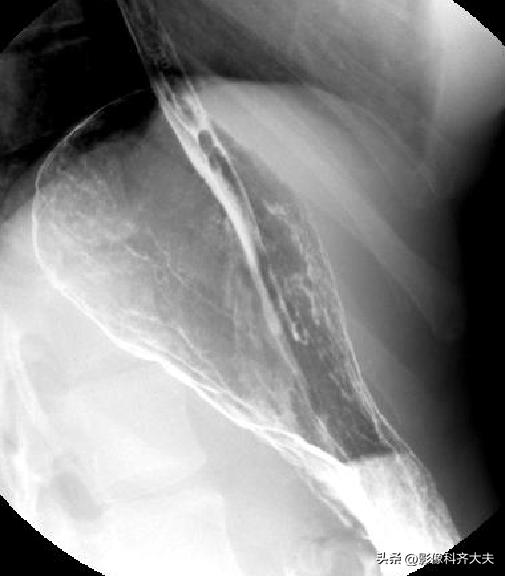

食管双对比相(站立右前斜位)

食管充盈相或粘膜相(站立右前斜位)